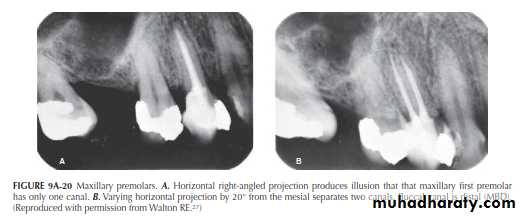

Maxillary Premolars

Variance in the horizontal projection has great value in maxillary premolar radiography, particularly for the first premolar, that generally has two roots and canals, but sometimes three. The clinical efficacy of the Walton (SLOB) technique is well illustrated in Figure 9A-20 The right-angle horizontal projection produces the single canal image seen in Figure9A-20A. By varying the angulation by 20°, however, thetwo canals are separated (Figure 9A-20B), giving an unobstructed view of the obturation quality in both canals.